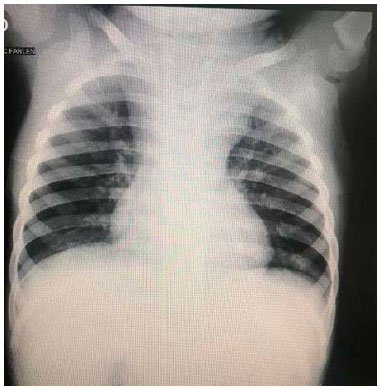

INFILTRAZIONE LEUCEMICA LINFADENOPATIA Leucemia acuta, sottotipo a cellule T radiografie del torace di un bambino di 4 anni che mostrano (a) slargamento mediastinico causato da ingrossamento timico;. A piccole cellule massa centrale con adenopatia ilare;. • segni legati alla presenza di ematoma mediastinico slargamento del profilo del mediastino.

INFILTRAZIONE LEUCEMICA LINFADENOPATIA Leucemia acuta, sottotipo a cellule T radiografie del torace di un bambino di 4 anni che mostrano (a) slargamento mediastinico causato da ingrossamento timico;. Il mediastino è un compartimento anatomico a forma di clessidra che occupa lo spazio centrale del torace compreso tra i polmoni, in cui sono contenuti il cuore, i grandi vasi ed altre strutture Tutti gli organi e strutture in esso contenuti (cuore, esofago, trachea, grossi vasi e numerosi linfonodi) possono dare luogo a patologie che prendono il nome di "mediastiniche". Mediastino translation in ItalianEnglish dictionary Showing page 1 Found 97 sentences matching phrase "mediastino"Found in 6 ms.